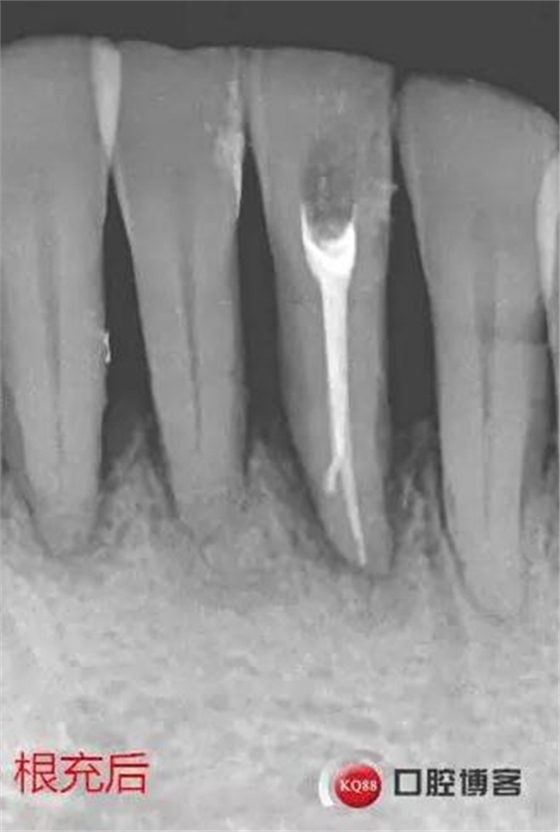

處理:31去暫封,疏通根管,沖洗,試尖,拍片,根充,拍片,恰填,根尖孔外無(wú)多余藥物滲出。樹脂充填開髓孔。33-43樹脂纖維帶固定,調(diào)合拋光。

由于兩次根管內(nèi)封藥后,頰根處均有多余藥物擠出根尖孔,考慮根尖孔處受破壞或根尖周炎癥導(dǎo)致牙周膜疏松,故封藥兩周后復(fù)診。